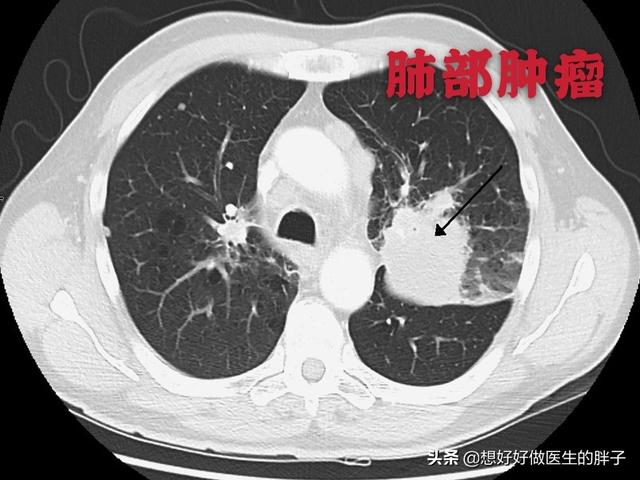

左肺にあるこの不規則な結節が原発巣で、わずか2.6cmしかない。このような骨転移を伴う肺がんは、もはや手術不可能です。肺がんはあまりにもありふれた病気であり、初期症状の中には非典型的なものや無症状のものさえあるからだ。肺がんの約30%では、転移の症状が最初の症状であり、さらなる肺がんが発見される前に転移が最初に発見される。